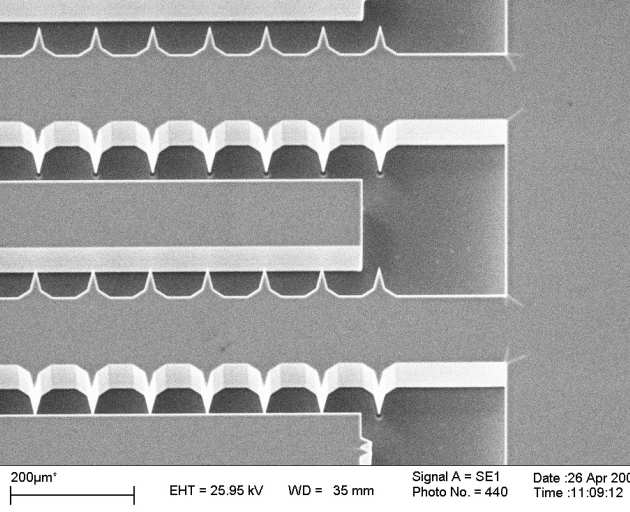

| a) external coil, b) internal coil, c) integration on duodenoscope, d) variable transformer, e) variation of mutual inductance with angle. |